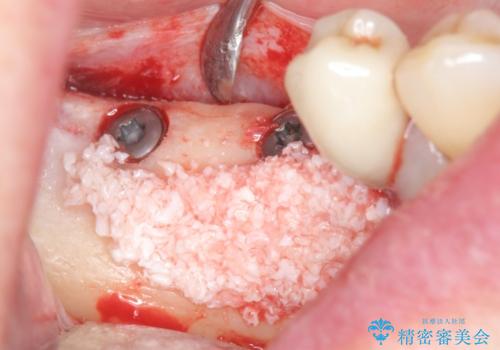

骨の造成を同時に行うインプラント治療

骨は薄くなってしまい、インプラントの長期的な安定を見込むには不十分でしたのでインプラントの埋入と同時に周囲にコツの造成を行う治療計画を立てます。

- 81.4万円 (straumann社製インプラント×2 アバットメント×2 仮歯×2 骨造成 ジルコニアクラウン×2)費用は治療当時の料金となります